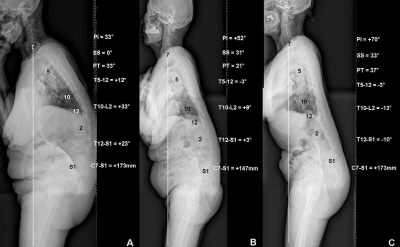

³í¹®¿¡¼­´Â ÅðÇ༺ ¿äÃß Èĸ¸Áõ ȯÀÚ 172¸í°ú °Ç°­ÇÑ ¼ºÀÎ 39¸íÀ» °ñ¹Ý ÀԻ簢¿¡ µû¶ó low, middle, high ±×·ìÀ¸·Î ³ª´©°í °ñ¹Ý ÀԻ簢, õÃß °æ»ç°¢, °ñ¹Ý °æ»ç°¢, ÈäÃß Èĸ¸ºÎ, Èä¿äÃß ¿¬Á¢ºÎ, ¿äÃß Àü¸¸ºÎ, ½Ã»ó ¼öÁ÷Ãà µî ôÃß-°ñ¹Ý ÁöÇ¥µéÀÇ ¿¬°ü°ü°è¸¦ ºñ±³ ¿¬±¸Çß´Ù.

±× °á°ú °ñ¹Ý ÀԻ簢ÀÌ Å« high ±×·ìÀº ¿äÃß Àü¸¸°¢ÀÌ ºñ±³Àû À¯ÁöµÊ¿¡µµ ºÒ±¸ÇÏ°í °ñ¹Ý ½ÅÀü±ÙÀÇ ¾àÈ­·Î ôÃß ¸ð¾çÀÌ ¾ÕÀ¸·Î ±Á´Â ½Ã»óºÒ±ÕÇüÀ¸·Î ÁøÇàµÇ°í, °ñ¹Ý ÀԻ簢ÀÌ ÀÛÀº low ±×·ìÀº ¿äÃß Èĸ¸Áõ°ú ÇÔ²² µî-Ç㸮ÀÇ Èĸ¸Áõµµ ÇÔ²² ÁøÇàÇϸç ôÃß ¸ð¾çÀÌ ¾ÕÀ¸·Î ±Á´Â ½Ã»óºÒ±ÕÇüÀ¸·Î ÁøÇàµÈ °ÍÀ¸·Î ³ªÅ¸³µ´Ù.